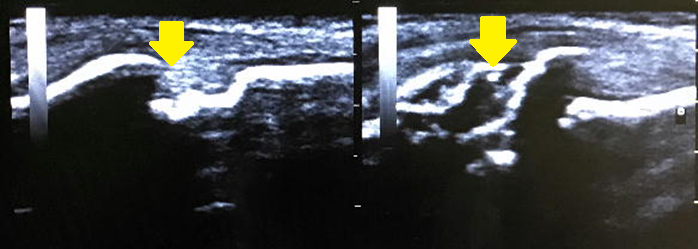

※画像:左が健側、右が患側です。

【症例3 膝の成長痛(オスグット・シュラッター病)】

小学6年生サッカー。強いシュートを打つと膝が痛く、走るのも徐々に辛くなって来院。

脛骨粗面での骨端線部位の骨輪郭に大きな乱れを認める。(程度の強い成長痛)